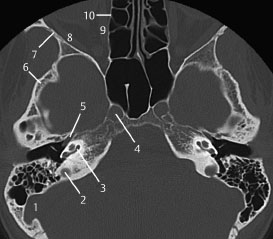

5 internal occipital protuberance. 4 mastoid air cells. 3 anterior clinoid process.

Ct anatomy of skull base. Blue central skull base csb purple posterior skull base teal anterior skull base asb. Foramina of the skull base and the structures that pass through them.

Cranial foramina for further details. A axial three dimensional reconstructed ct image with color coded overlay shows the skull base sections. Ct anatomy of skull base.

Blue temporal bones fuchsia nasal bones green ethmoid bone light pink vomer purple occipital bones teal sphenoid bone yellow zygomatic bones. Basic anatomy review the bones sutures and fissures that comprise the skull base. Detailed anatomy enter this module for a more detailed review of skull base anatomy.

The base of the skull is perforated by numerous foramina which allow vessels and nerves to pass through the base of the skull allowing the intracranial cavity to communicate with the rest of the body see main article. Skull ct anatomy the sagittal suture is the line where the right and left parietal bone are in contact. A noncontrast sinus or skull base ct which covers the mastoids temporal bone and entire skull base is recommended and intravenous contrast is not usually necessary as the mri will provide soft tissue detail.

Ct is more sensitive in detecting fibro osseous skull base lesions calcification and sclerosis. The module interface is meant to mimic a radiology workstation with adjacent image scrolling via arrow keys and or mouse wheel button. Navigating the skull base identify the petro occipital fissure to navigate the major structures of the skull base.